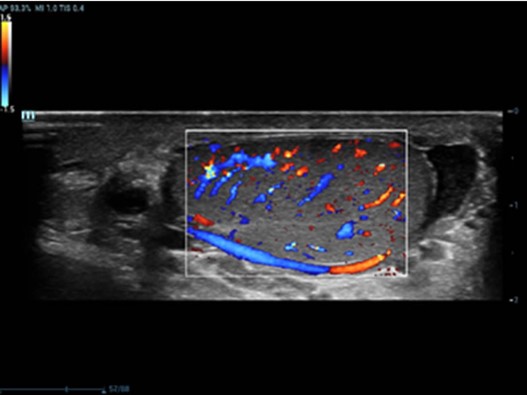

Resona 7, ĂŒstĂŒn dĂŒzeyde g?rĂŒntĂŒ kalitesine ek olarak, vaskĂŒler hemodinamik de?erlendirmesi i?in devrim niteli?indeki V Ak??? ile fetĂŒs CNS tan?lamas? i?in 3 boyutlu veri kĂŒmesinden dĂŒzlem g?rĂŒntĂŒsĂŒ alma konusunda en iyi birime sahip oldu?undan, klinik ara?t?rma yeterliklerini de art?rmaktad?r. En sezgisel, harekete dayal? ?oklu dokunmatik i?letim ile tĂŒm temel klinik ?zellikleri bir araya getiren Resona 7, ultrason yenili?i konusunda ger?ek anlamda yeni dalgalara ?ncĂŒlĂŒk ediyor.